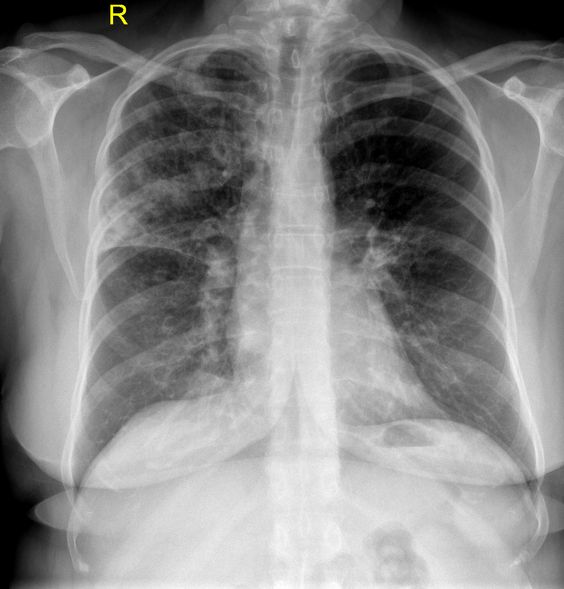

Lobar consolidation involving the right middle lobe, right lower lobe | Download Scientific

Lobar consolidation involving the right middle lobe, right lower lobe | Download Scientific  ENFISEMA LOBAR CONGENITO PDF

Lobar pneumonic consolidation in the right inferior lobe | Download Scientific Diagram  ENFISEMA LOBAR CONGENITO PDF

Lobar consolidation | Radiology Reference Article | Radiopaedia.org  PPT - Atelectasis PowerPoint Presentation - ID:6185976

Chest radiograph reveals multi-lobar consolidation in bilateral lower | Download Scientific  Bilateral multifocal acute lobar nephronia caused by Enterococcus faecalis | BMJ Case Reports